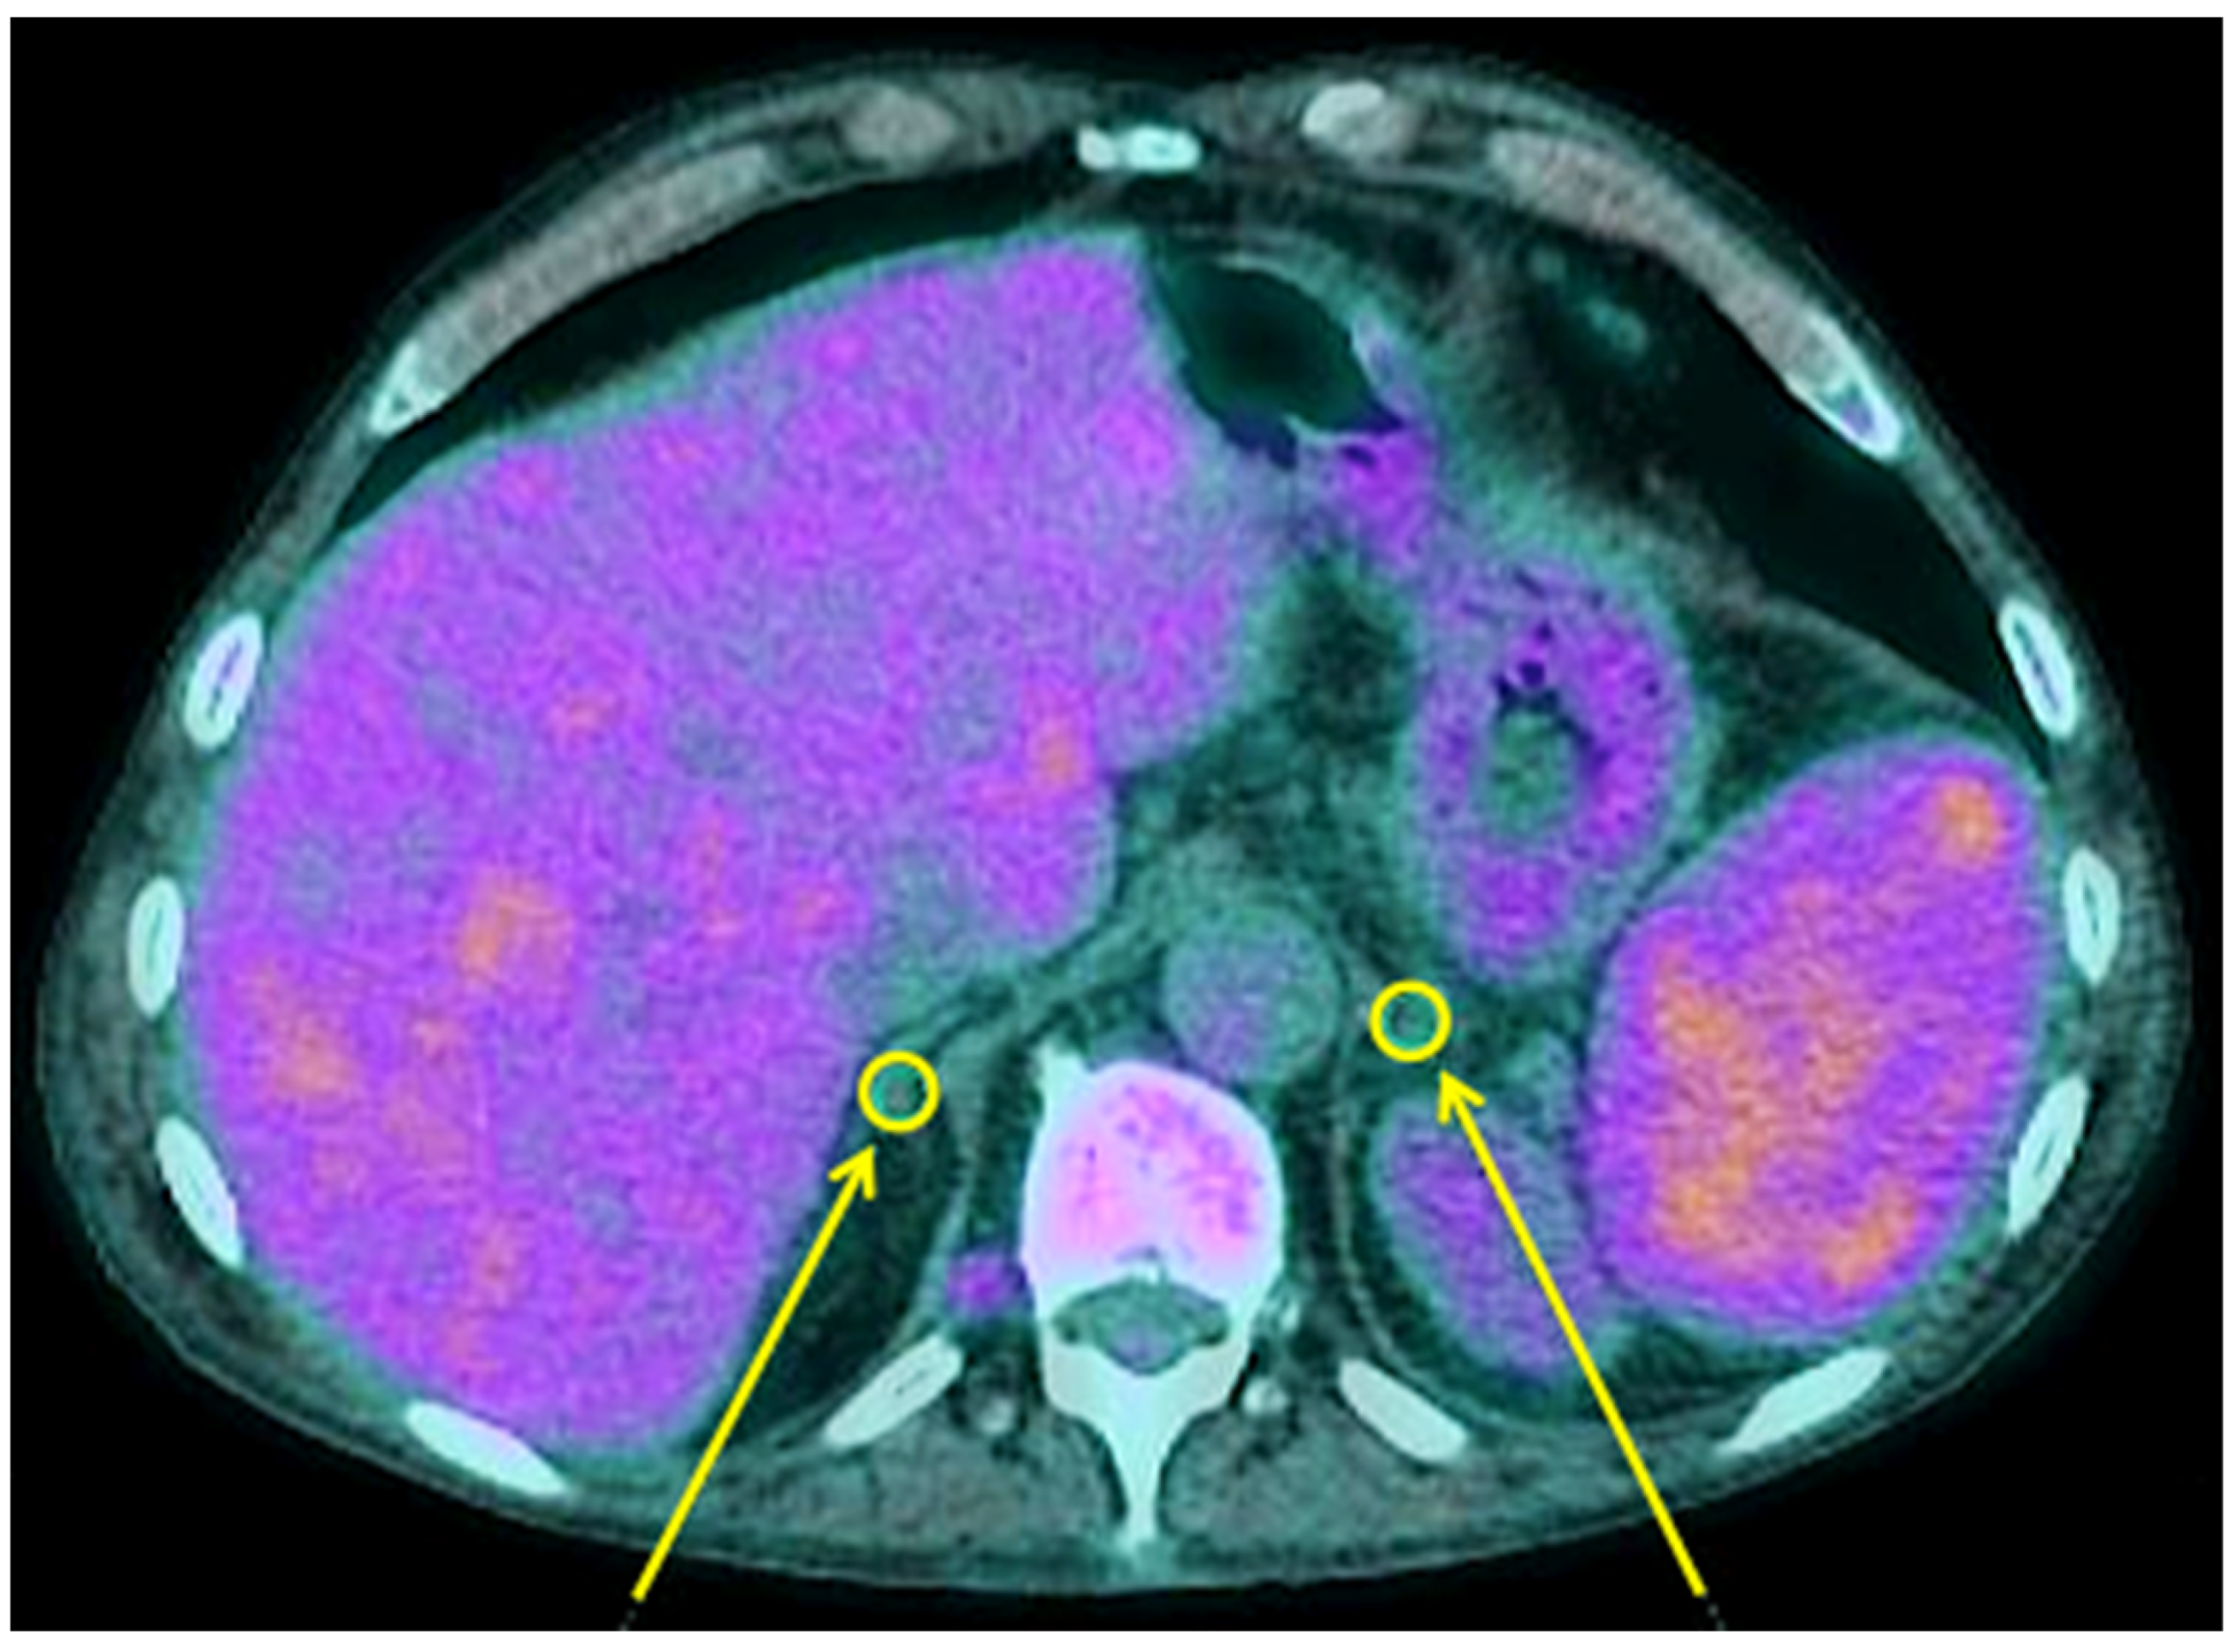

3.2. Thyroid and Adrenal Gland Analysis